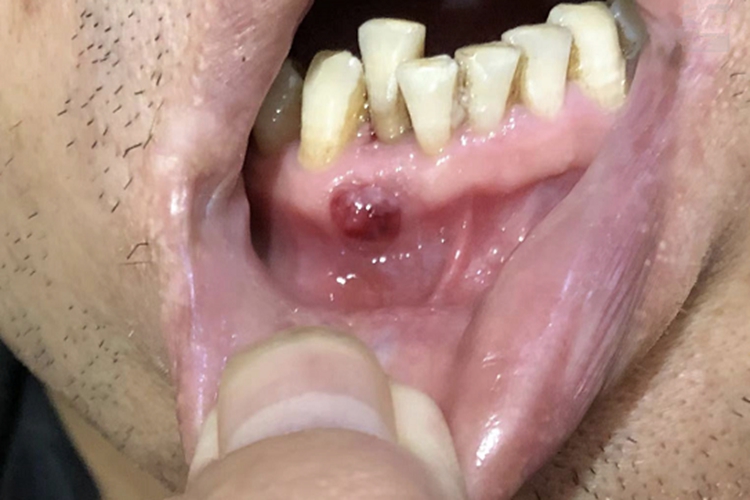

急性化脓性根尖周炎的黏膜损害可发生在口腔,临床可表现为局部肿胀,表面出现疙瘩,明显突出于黏膜表面,呈球形损害,内含血性脓液或黄白色脓液,伴有一定的疼痛感,在进食时疼痛感更加明显。

急性化脓性根尖周炎的治疗原则是消炎止痛,待症状缓解后采用根管治疗或牙髓塑化治疗。消炎止痛处理时,需要对根尖周组织的炎症渗出液进行引流,缓解局部压力。若存在黏膜下脓肿,已有根尖部的波动感,还应切开脓肿,以便脓液引流,以上治疗均需遵医嘱进行。